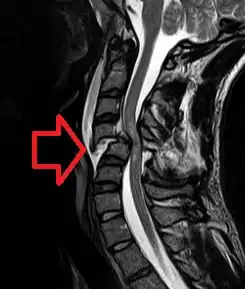

A radiographic evaluation using an X-ray, CT scan, or MRI can determine if there is damage to the spinal column and where it is located.[9] X-rays are commonly available[88] and can detect instability or misalignment of the spinal column, but do not give very detailed images and can miss injuries to the spinal cord or displacement of ligaments or disks that do not have accompanying spinal column damage.[9] Thus when X-ray findings are normal but SCI is still suspected due to pain or SCI symptoms, CT or MRI scans are used.[88] CT gives greater detail than X-rays, but exposes the patient to more radiation,[90] and it still does not give images of the spinal cord or ligaments; MRI shows body structures in the greatest detail.[9] Thus it is the standard for anyone who has neurological deficits found in SCI or is thought to have an unstable spinal column injury.[91]